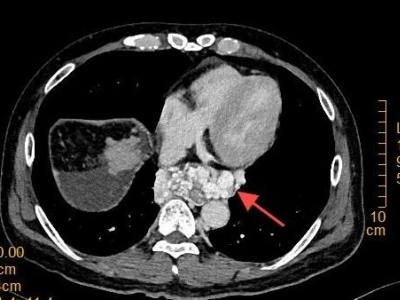

【特色医疗】“翻修两条路,搭起一座桥” 市中心医院成功救治复杂门静脉病变患者